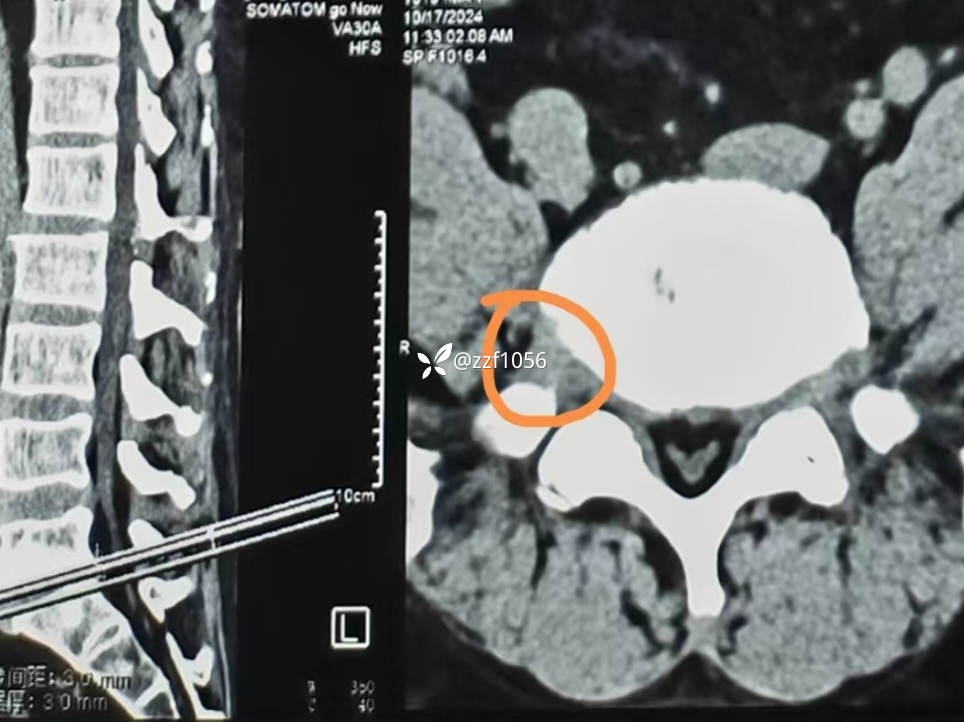

右侧减压彻底,L5S1根松弛,保留了左侧关节突所以撑开有限,使用8mmCage

影像上可看到L5/S1间隙非常狭窄,退变严重,两侧均有神经根激惹,椎间孔狭窄,L5下终板终板炎较重,左下肢无任何症状,右下肢L5S1根症状均存在,建议椎间孔镜下减压L5根和S1根,患者拒绝,因咨询多家医院要求开放融合。

目前患者已拆线,腰封保护下下床行走可,疼痛症状消失,右足麻木稍改善,肌力仍3级群,继续康复。